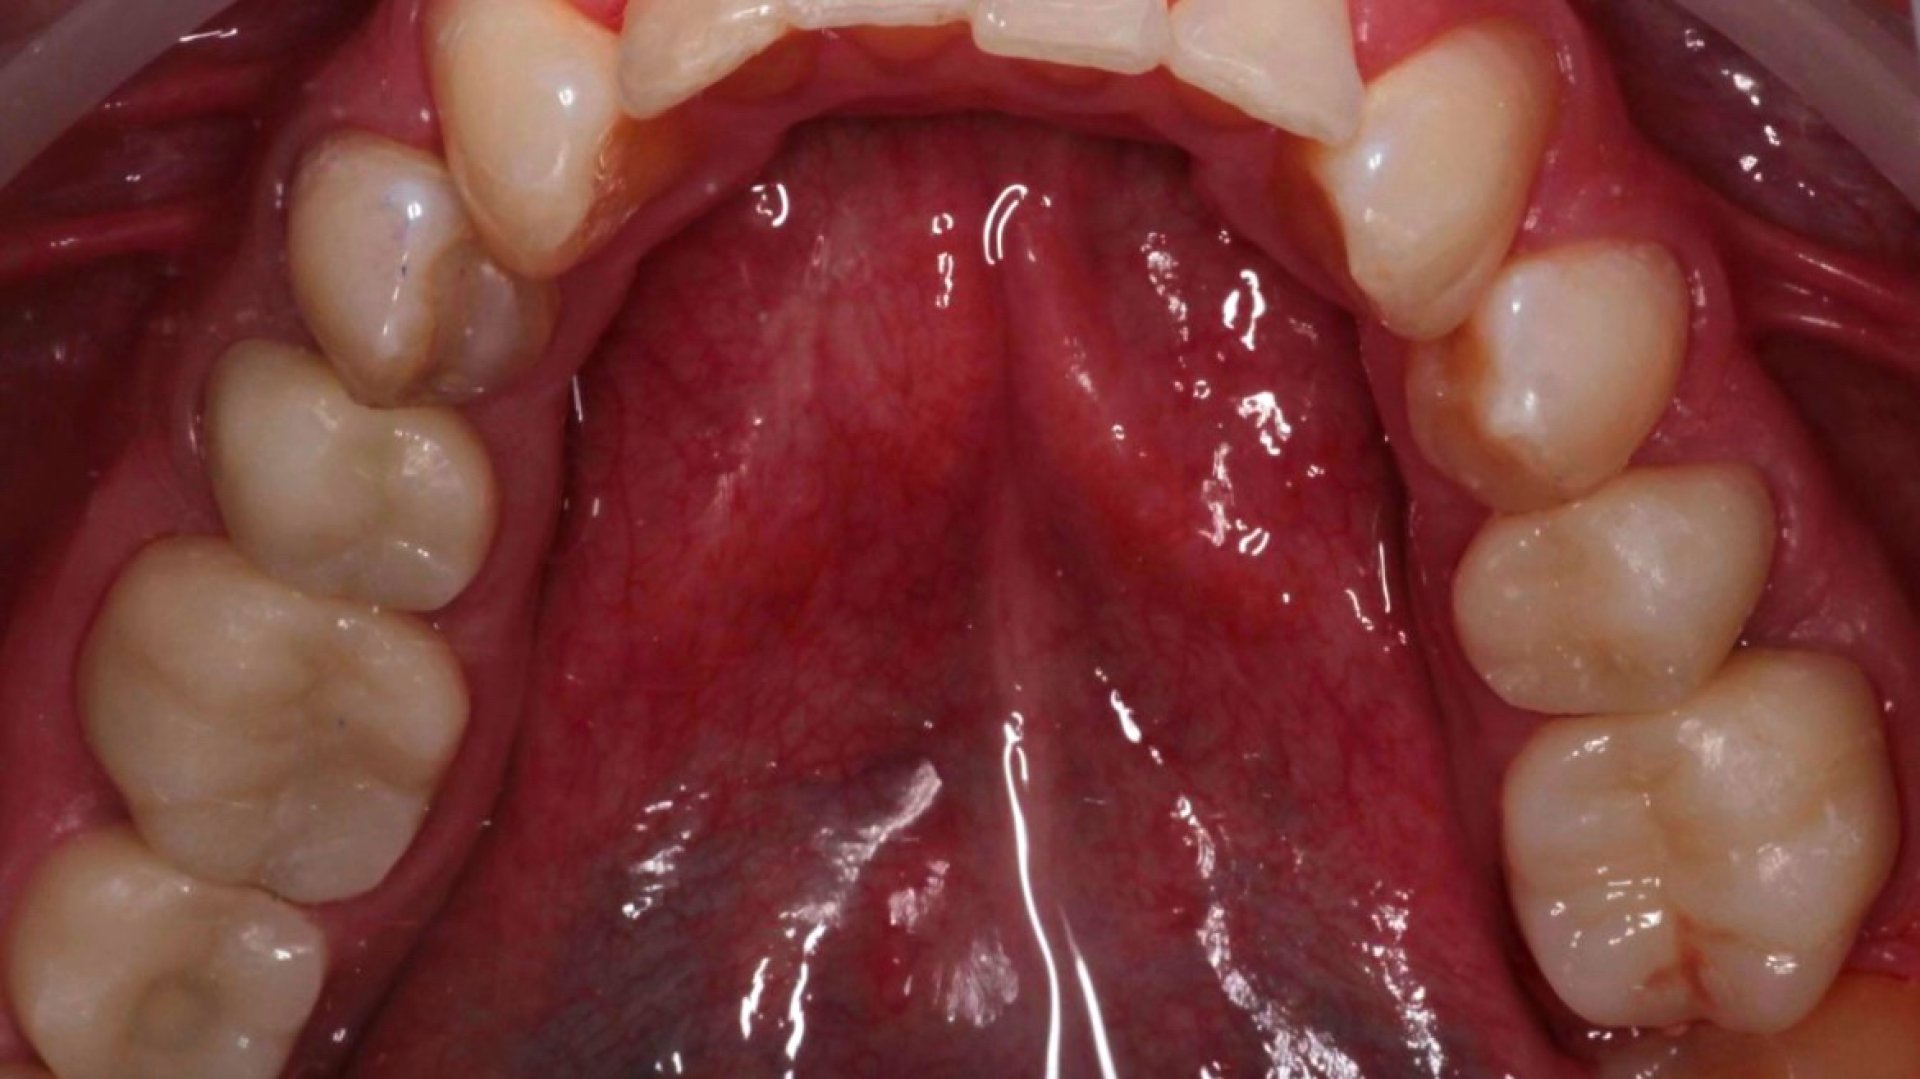

До

Циркониевые коронки на жевательные зубы. 3.5-3.6, 4.5-4.6_before